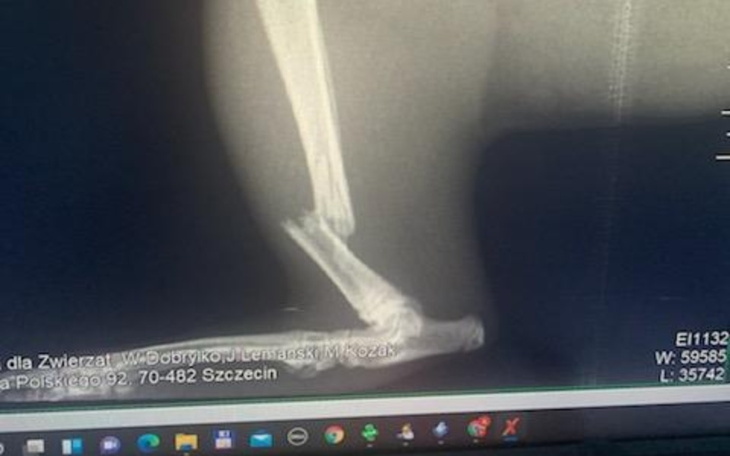

Pilnie potrzebna pomoc. Moj kotek zwalil na siebie ciężka belę foli. Skończyło się skomplikowanym złamaniem z przemieszczeniem prawej nóżki. Konieczna jest natychmiastowa operacja Koszt w Szczecinie niestety na ten moment przekracza moje mozliwosci - 1800 zl. Znalazlam weta w Gryficach ktory zgodzil się przeprowadzic operacje za 1000 zl i rozlozyc spłatę na dwie raty.

Edyt. Wczoraj odbyła się operacja. Dwie sruby i blaszka żeby ustabilizowac kosc. Było ciężko i dalej ciezko jest bo kotek cierpi. Robię zastrzyki przeciwbolowe, przeciwzapalne i z antybiotyku.